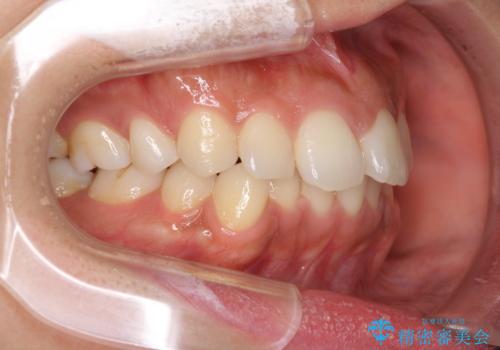

前歯の叢生の改善を目的として、IPR(歯と歯の間を削る)と歯列全体の後方移動によって歯並びを整えることとしました。

臼歯部も含め、叢生が綺麗に改善され、患者様には大変満足していただきました。